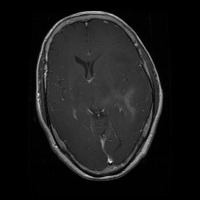

This project has created a labeled MRI brain tumor dataset for the detection of three tumor types: pituitary, meningioma, and glioma. The dataset contains 2443 total images, which have been split into training, validation, and test sets. The training set has 1695 images, the validation set has 502 images, and the test set has 246 images.

- Image types: MRI scans

Classes:

- Pituitary tumor

- Meningioma tumor

- Glioma tumor

- No Tumor

- The images have been labeled by medical experts using a standardized labeling protocol.

- The labels include the type of tumor and the location of the tumor.